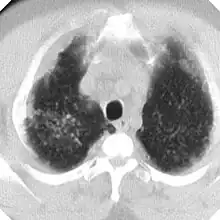

En caso de dudas diagnósticas se puede recurrir a la Tomografía Computada de Alta Resolución (TACAR) que se ha mostrado más sensible y específica para el diagnóstico.[9] Somete al paciente a mucha más radiación que la Rx y no debe usarse como prueba diagnóstica de primer nivel sino para aclarar dudas. La TACAR permite comprobar cómo las masas de FMP se originan frecuentemente en región subpleural de zonas apicales posteriores desplazándose progresivamente de la pleura —signo del desprendimiento—.[3]

La silicosis complicada se caracteriza por la presencia en los pulmones de masas de diámetro superior a 1 centímetro llamadas masas de Fibrosis Masiva Progresiva (FMP) que al retraerse generan bullas en su periferia y distorsionan los bronquios determinando obstrucción y limitación del flujo aéreo, aparte de otras complicaciones (neumotórax, cavitación aséptica, cavitación por tuberculosis, etc). Si las masas alcanzan cierto tamaño alteran notablemente los parámetros de función pulmonar, tanto de ventilación como de intercambio de gases. Silicosis aguda, la cual resulta de la exposición a cantidades muy grandes de sílice durante corto tiempo. Los pulmones se inflaman bastante y se pueden llenar de líquido, lo que causa una dificultad respiratoria grave y una baja de los niveles de oxígeno en la sangre.